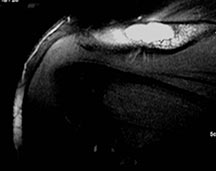

Sites:

- Flat Bones (most common—70%)

- Skull

- Pelvis

- Femur

- Humerus

- Hands and Feet are rare in solitary disease